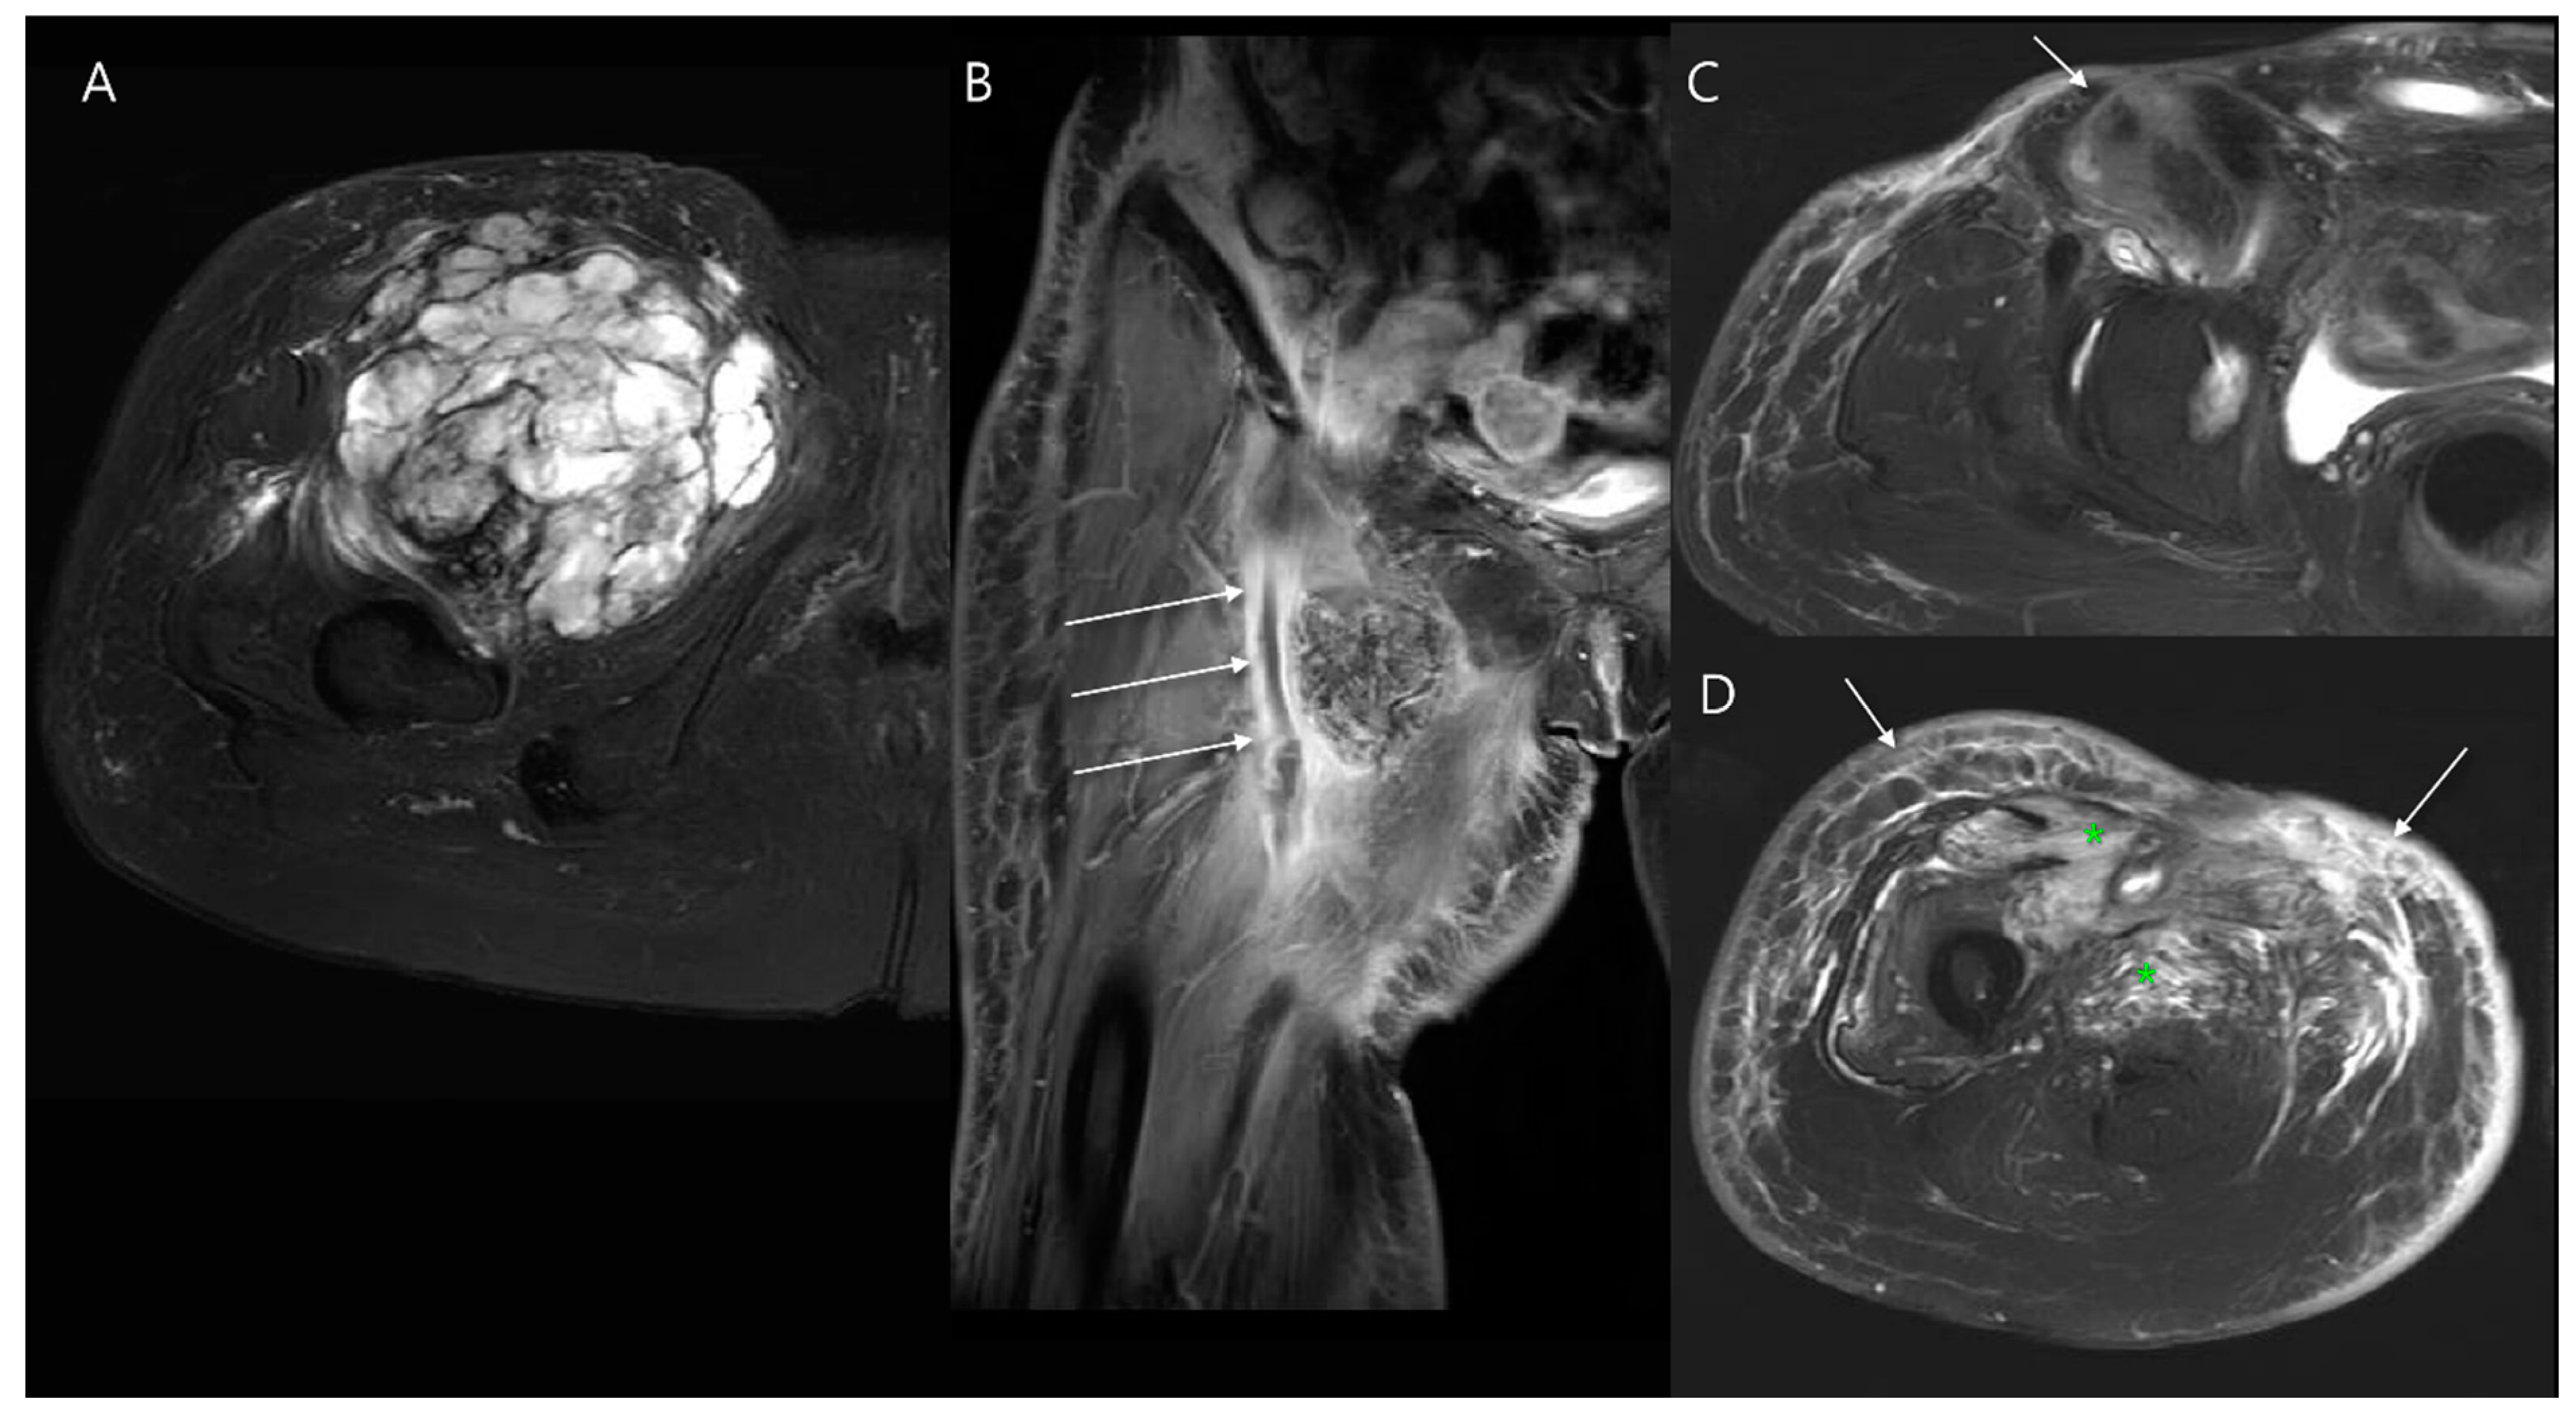

- Olapoju, O.M.; Botros, J.; Damani, B.; Tiesenga, F. Chronic Expanding Hematoma in the Upper Extremity: A Case Report on Diagnostic and Management Challenges. Cureus 2024, 16, e62330. [Google Scholar] [CrossRef]

- Liu, P.T.; Leslie, K.O.; Beauchamp, C.P.; Cherian, S.F. Chronic expanding hematoma of the thigh simulating neoplasm on gadolinium-enhanced MRI. Skelet. Radiol. 2006, 35, 254–257. [Google Scholar] [CrossRef]

- Reid, J.D.; Kommareddi, S.; Lankerani, M.; Park, M.C. Chronic expanding hematomas. A clinicopathologic entity. JAMA 1980, 244, 2441–2442. [Google Scholar] [CrossRef]

- Serra Del Carpio, G.; Tapia Viñé, M.; Torena, N.; Bernabeu Taboada, D. Chronic expanding hematoma. Radiología 2023, 65 (Suppl. 2), S78–S82. [Google Scholar] [CrossRef]

- Galantini, G.; Mushtaq, B.; Ottaway, J.; Long, C.D. Successful Treatment of a Chronic Recurrent Expanding Hematoma of the Thigh. Plast. Reconstr. Surg. Glob. Open 2024, 12, e6133. [Google Scholar] [CrossRef] [PubMed]

- Song, E.H.; Lee, S.Y.; Lee, S.; Jung, J.Y.; Shin, S.H.; Chung, Y.G.; Jung, C.K. Diagnosis of Local Recurrence of Malignant Soft Tissue Tumors after Reconstructive Surgery on MRI. J. Clin. Med. 2023, 12, 4369. [Google Scholar] [CrossRef]

- Tavare, A.N.; Robinson, P.; Altoos, R.; LiMarzi, G.M.; Scherer, K.F.; Kransdorf, M.J.; Bancroft, L.W. Postoperative Imaging of Sarcomas. Am. J. Roentgenol. 2018, 211, 506–518. [Google Scholar] [CrossRef] [PubMed]

- Sedaghat, S.; Salehi Ravesh, M.; Sedaghat, M.; Meschede, J.; Jansen, O.; Both, M. Does the primary soft-tissue sarcoma configuration predict configuration of recurrent tumors on magnetic resonance imaging? Acta Radiol. 2022, 63, 642–651. [Google Scholar] [CrossRef]